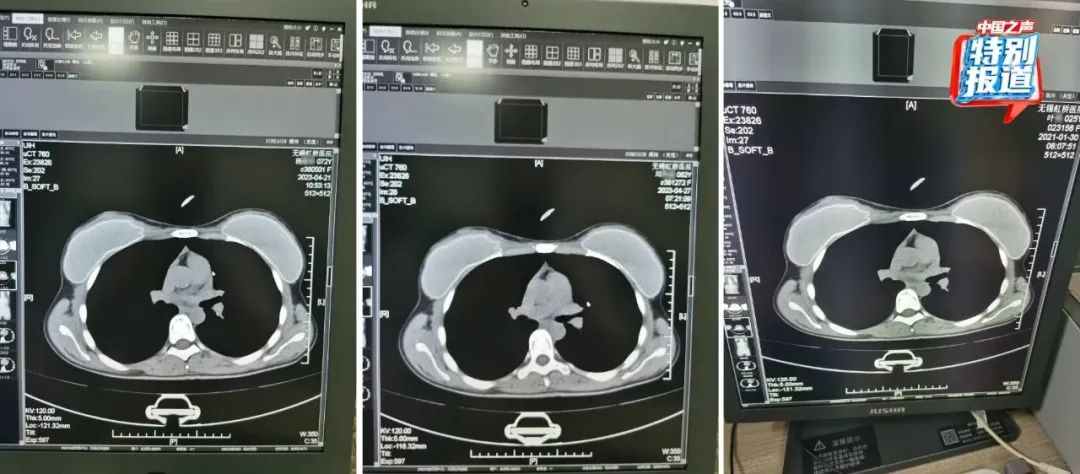

在被举报的病历中,杨某某(72岁)和邱某某(62岁)的病历里,有根据所拍片子的情况做出的诊断,却找不到对应的影像。6月份又查到了她们的CT影像,片子上清晰看出,两位患者的吊坠形状、大小和位置都基本一致。

不仅这两位患者CT影像类似,朱成刚比对发现,2021年做过CT的25岁女性叶某的片子上,也有看起来极为相似的吊坠,肉眼看,三人的片子几乎一模一样。

72岁的杨某某、62岁的邱某某与25岁的叶某,三人的片子几乎一模一样。

类似这样看上去雷同程度很高的片子,还有不少。